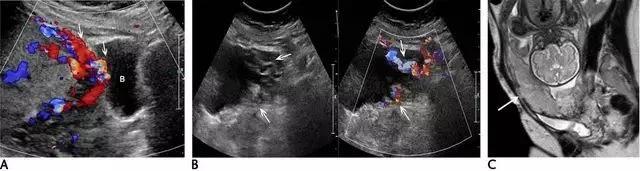

滋养层胎盘肿瘤包括一组源于胎盘滋养策划的相关肿瘤,如部分性及完全性葡萄胎、侵袭性葡萄胎、绒癌、胎盘滋养层肿瘤。引起本病的风险因素包括高龄孕妇与既往患过胎盘滋养层肿瘤病史。部分或完全性葡萄胎是良性病变,部分性葡萄胎伴有胎儿存活,而完全性葡萄胎没有胎儿,其患绒癌的风险性更大。在超声上,葡萄胎的子宫增大,部分性葡萄胎的子宫可见多个弥漫性无回声病变,胎儿因多发先天性畸形、三倍体及生长受限而不能存活(图 16)。

图 16 示部分性葡萄胎:A 为子宫横断面,箭头示宫内不均质囊实性包块,血流丰富,宫内可见积液。B 示宫内另可见部分胎儿(小箭头)及较短的脐带(长箭头、)。C 为盆腔矢状位的压脂像 T2WI,上方箭头示宫内不均质包块,下方箭头示部分胎儿

完全性葡萄胎在早孕期呈现为子宫增大、宫腔充满不均质的伴血流的高回声策划,宫内可出现小囊肿,可误认为早孕。妊娠后期时,宫内充满高回声包块,内含多个无回声囊性暗区(即水肿的绒毛),称为「瑞士奶酪」或「暴风雪」 征(图 17)。双侧卵巢可有黄素囊肿(即较大的多分隔囊肿),系 HCG 增高引起。宫内包块为高速低阻血流,与宫内正常弓状低速低阻血流不同。在双卵双胎妊娠,可同时并存葡萄胎与正常妊娠。此时,正常胎儿可有正常胎盘,这与部分性葡萄胎不同。

图 17示完全性葡萄胎:孕 10 周时的子宫纵切面,宫内充满囊性包块,患者的 HCG 显著升高。虽超声怀疑肌层遭侵润,但经 MRI 予以排除

葡萄胎可分化为侵袭性葡萄胎及胎盘位置的滋养细胞肿瘤或绒癌。侵袭性葡萄胎的特点是滋养层的过度生长,并子宫肌层的广泛深度渗入;这种侵袭过程为局部性的,并未发生转移,与绒癌不同。在超声上,侵袭性葡萄胎的包块为高速、低阻性血流,其阻力指数尚低于完全性葡萄胎的阻力指数(图 18)。

图 18 为侵袭性葡萄胎:孕妇 35 岁,曾患完全性葡萄胎、并接受清宫,现在 HCG 持续升高。此图示宫腔扩张,内充满不均质的软策划,血流丰富,内膜与肌层的界限消失(箭头)。超声还可见较大的多房性卵巢囊肿(黄素囊肿,此图未显示)